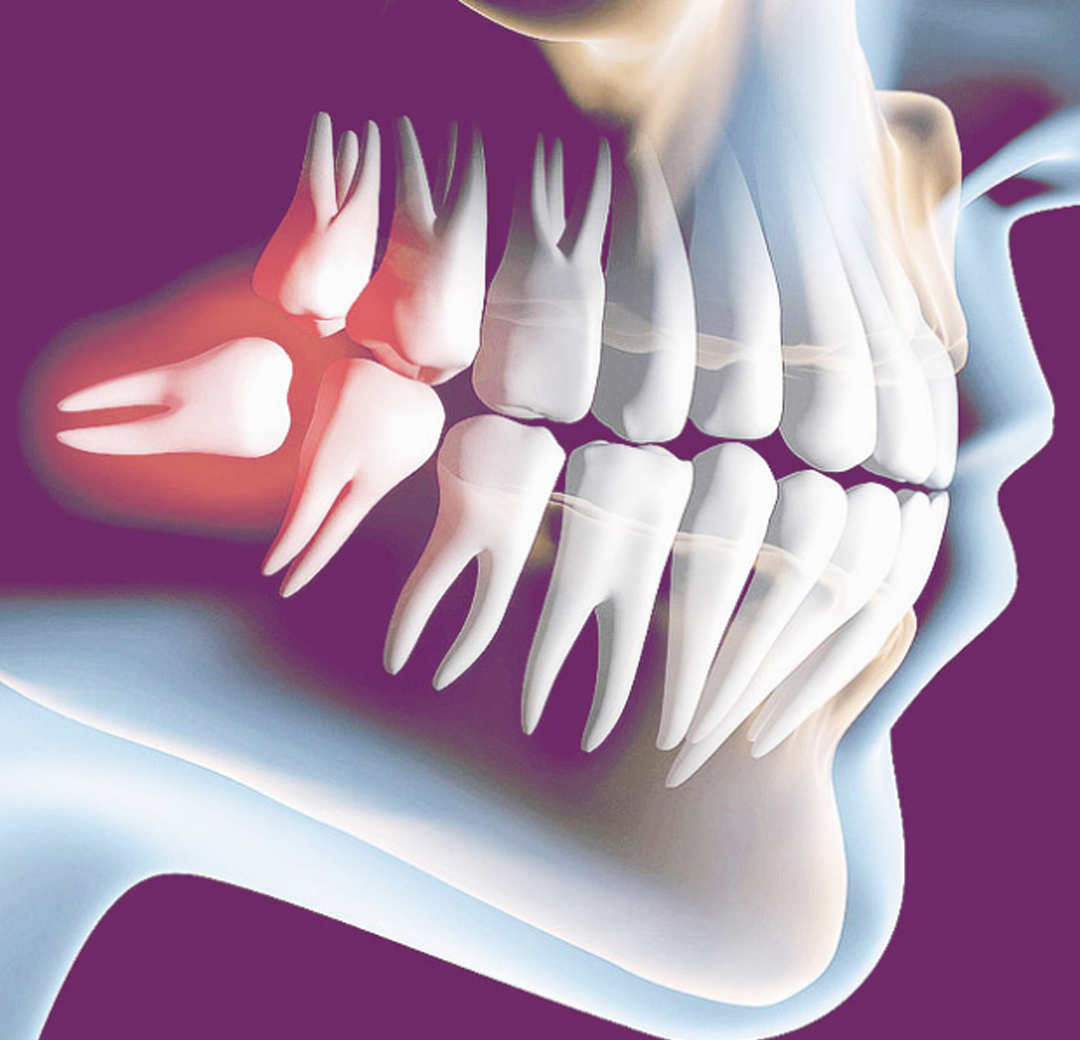

Os terceiros molares, conhecidos como dentes sisos, são os últimos dentes da boca. E correspondem a quatro dentes no total, dois superiores e dois inferiores. A extração do dente siso pode ou não ser necessária.

A extração do dente siso é indicada em algumas situações, dentre elas temos a falta de espaço na arcada, questões protéticas e/ou ortodônticas, presença de infecção em uma maior porção do dente ou do osso ao redor, lesões cariosas devido a incapacidade de uma higiene adequada, entre outros fatores.

O siso pode interferir no alinhamento de outros dentes?

Sim. Como são os últimos dentes a nascer, pode ser que os mesmos não encontrem espaço suficiente na boca. Dessa forma, essa falta de espaço pode acarretar uma movimentação dos outros dentes, provocando assim um desalinhamento, que além de atrapalhar a estética, dificulta a higienização.

Correto. Muitas pessoas relatam desconforto quando os dentes sisos estão nascendo. Isso se deve, principalmente, ao acúmulo de bactérias no local, que pode acarretar em um processo inflamatório e até mesmo infeccioso. Além da dor, um inchaço na região pode estar presente e em situações mais severas o paciente desenvolve uma dificuldade de abertura bucal. É extremamente necessário realizar uma consulta com o dentista nessas situações, pois existe o risco dessas bactérias caírem na corrente sanguínea, comprometendo não somente o local em questão, mas o organismo como um todo. Por isso, em alguns casos, é necessário a extração do dente siso.